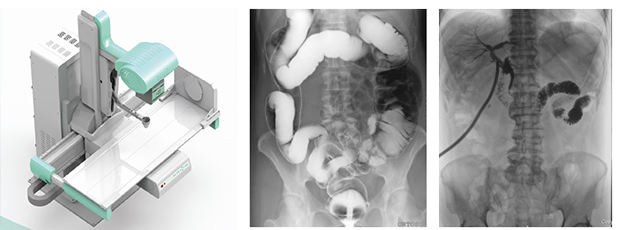

隨著現(xiàn)代醫(yī)療技術(shù)快速發(fā)展,傳統(tǒng)的X射線技術(shù)實現(xiàn)數(shù)字化,出現(xiàn)了多功能DR。多功能DR采用數(shù)字影像平板探測器取代傳統(tǒng)膠片,直接捕獲X線影像,并轉(zhuǎn)化為高清晰數(shù)字圖像,對比傳統(tǒng)的間接影像設(shè)備,多功能DR可以直接將X射線轉(zhuǎn)化成圖像,成像更清晰,放射劑量更小。

多功能DR大大提高了普通放射設(shè)備準(zhǔn)確診斷的能力,為臨床創(chuàng)造了價值,它可以進(jìn)行全身各部位的拍片、透視和點片攝影。接下來小編給大家介紹一下這三種模式的區(qū)別。

多功能DR

點片攝影是在透視的條件下,對病變部位進(jìn)行可視化觀察,待發(fā)現(xiàn)疑似病變部位的時候進(jìn)行瞬間點片,從而能夠準(zhǔn)確獲取病變部位的高清影像用于臨床診斷,從而在一定程度上降低漏診誤診率。病人不動,通過選擇鍵由透視直接切換攝影的曝光過程。在透視過程中,保存一幅靜止的圖像。常用于消化道、膽系造影下的攝影等。它既可以觀察運(yùn)動器官的運(yùn)動功能,又能在有感興趣的圖像時,對膠片曝光保留感興趣的圖像,便于進(jìn)一步診斷。